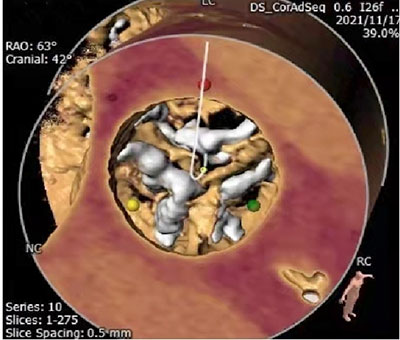

CT三维重建可以看到严重钙化的主动脉瓣膜